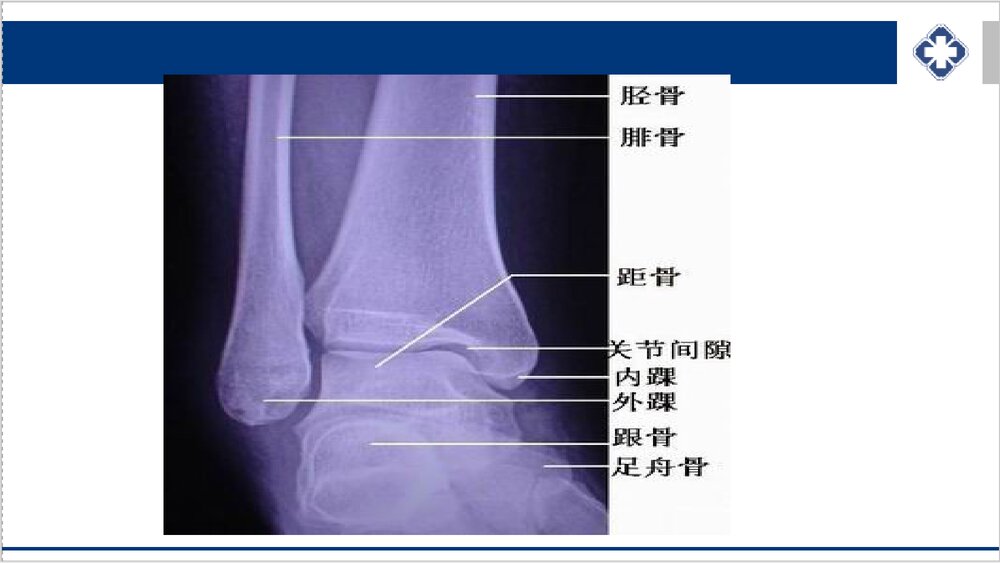

踝关节骨折的护理概要踝关节骨折较为多见,无论在日常生活中或运动场上均易发生。踝部骨折加上踝部韧带损伤,占全身损伤的4%~5%。踝部骨折多由间接暴力引起,如外翻、内翻或外旋等。踝关节是负重关节,骨折均为关节内骨折,若对位不好,将形成创伤性踝关节炎,伤踝僵硬疼痛、行走困难、痛苦甚大。多为骨与韧带的合并伤,应对骨折和韧带损伤同样重视和处理。解剖特点踝关节骨折是最常见的关节内骨折,多见于青壮年。胫骨远端内侧突出部分为内踝,后缘呈唇状突起为后踝,腓骨远端突出部分为外踝。内踝、外踝和胫骨下端关节面构成踝穴,包容距骨体。距骨体前宽后窄,踝关节背伸时,距骨体和穴适用性较好,踝关节稳定,反之,则踝关节不稳定而容易扭伤引起踝关节骨折。解剖概述踝关节的骨性结构由胫骨、...